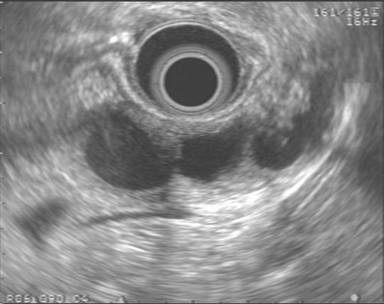

Figure 1. EUS findings in a 42-year-old female patient with a mucinous cystic neoplasm in the body of the pancreas. A cyst wall is present in addition to one tangential thin septum. The adjacent parenchyma appears unremarkable. No FNA was performed in this case and the patient was referred to surgery. |